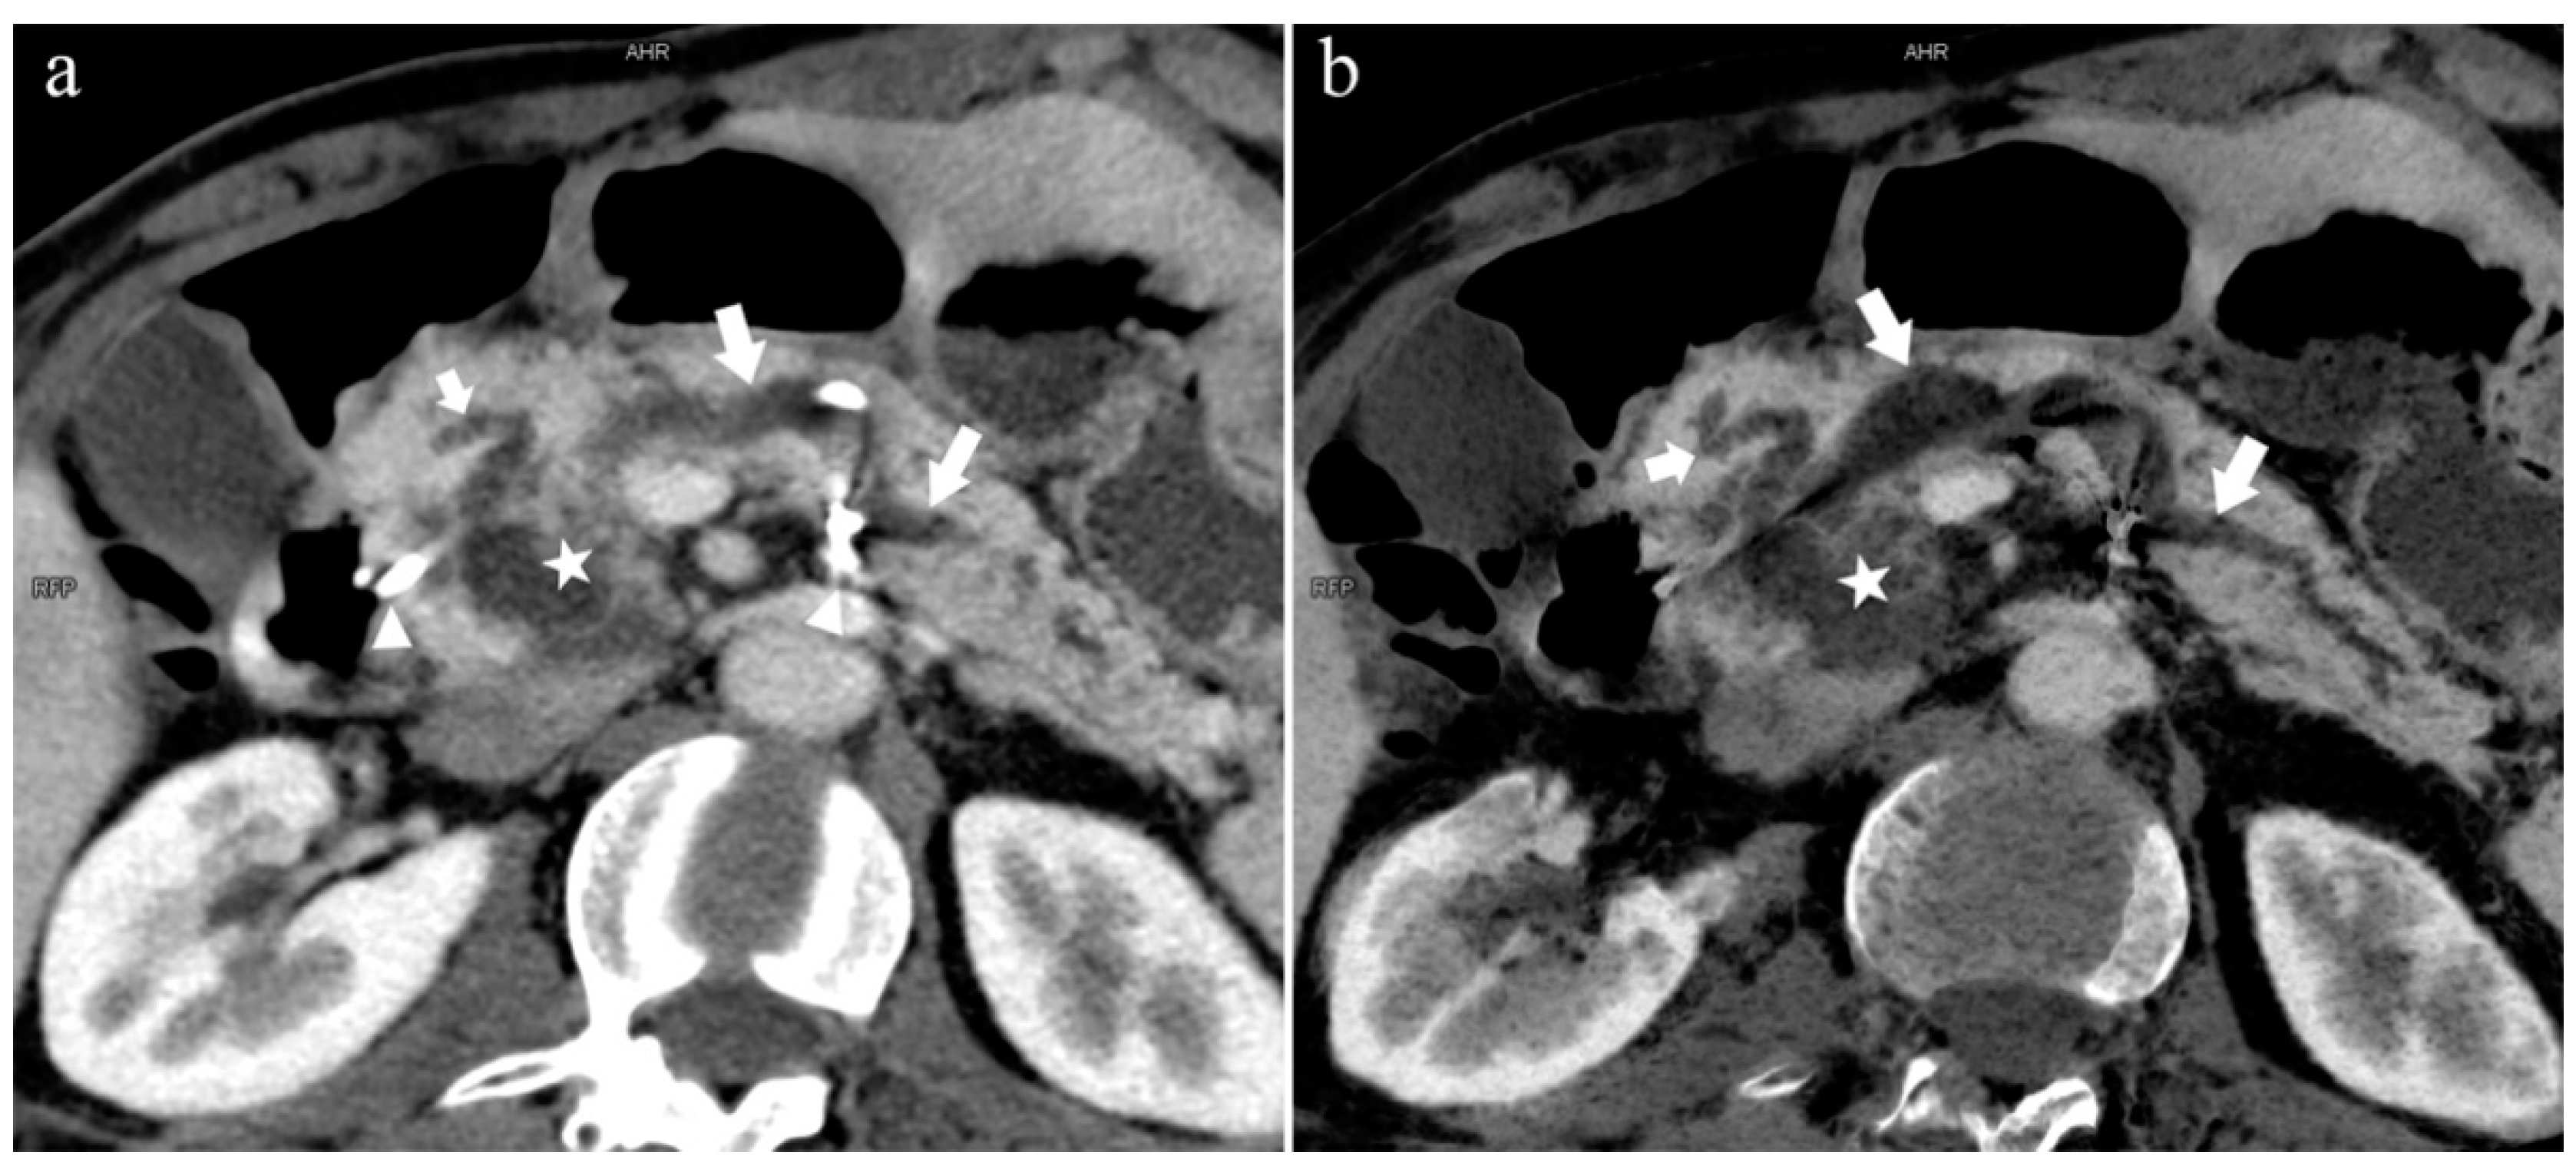

5.2. Special Types of Pancreatic Duct Variation

5.2.1. Pancreas Divisum (Type 4)

5.3.2. Pancreatitis